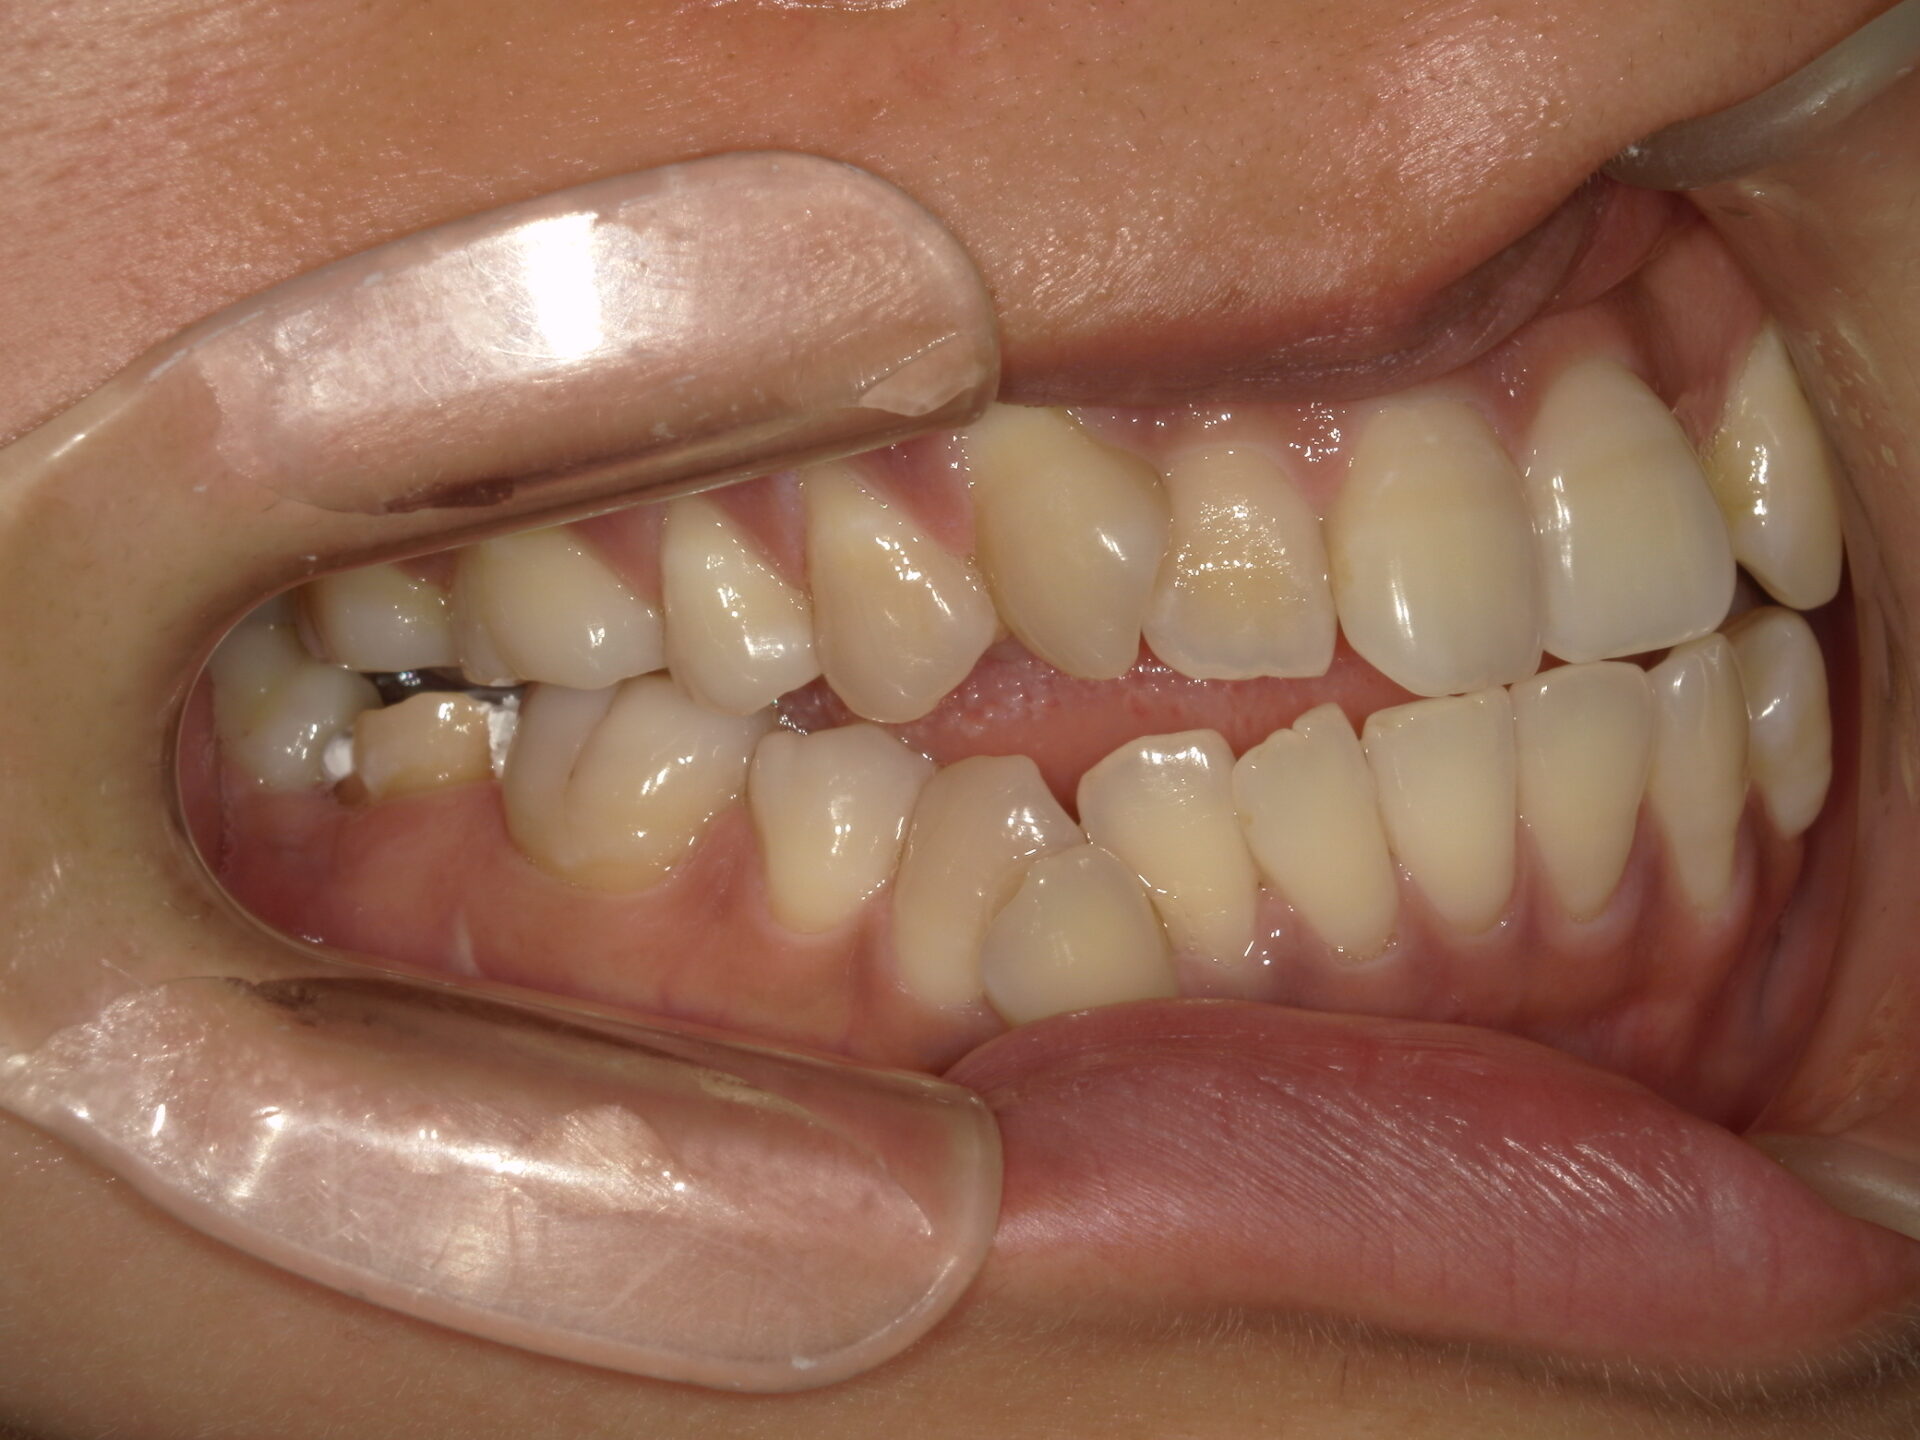

before

患者さんの年齢 20代 女性 症状 ガタガタを治したい 治療内容 マウスピース矯正治療 費用 90万(税抜) 治療期間・回数 治療期間2年、通院回数10回 メリット 笑顔が綺麗 デメリット・リスク 期間がかかることがある - マウスピース矯正